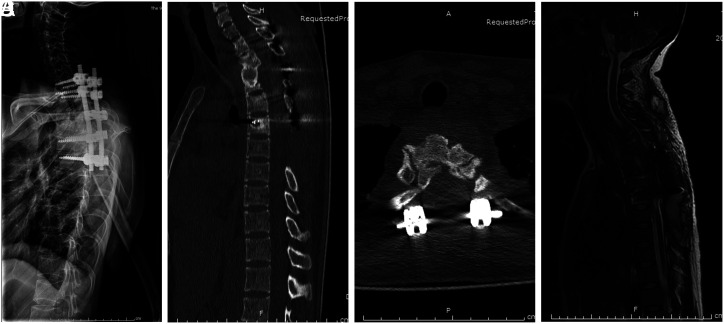

本研究旨在评估单纯后路清创、椎间融合和内固定术治疗上胸椎结核的有效性和可行性。本研究回顾性分析了 8 名确诊为上胸椎结核患者的临床和影像学数据。所有患者均接受了后路清创术、椎间融合术和内固定术。我们对视觉模拟量表(VAS)、Oswestry残疾指数(ODI)评分、红细胞沉降率(ESR)、C反应蛋白(CRP)、ASIA评分和椎体后凸Cobb角进行了术前和术后评估。背痛和下肢无力是最常见的症状。手术平均持续时间、失血量和术后引流量分别为 262.5 ± 43.3 分钟、625.0 ± 333.8 毫升和 285.0 ± 118.1 毫升。对患者进行了 36 至 48 个月的随访。术后三个月,VAS 和 ODI 评分明显改善,并在最后一次随访前进一步改善。术前和术后的差异有统计学意义(P < .05)。在最后的随访中,5 位瘫痪患者的下肢功能均已完全恢复正常。术后 3 个月内,血沉和 CRP 恢复正常,分别为 18.1 ± 7.3 mm/h 和 9.95 ± 5.41 mg/L。术前和术后存在统计学差异(P < .05)。平均畸形矫正率为 (71.5 ± 7.3)%,平均矫正角度损失为 (3.5 ± 1.4)°。所有患者均在术后 15 个月内(平均 8.3 ± 3.2 个月)实现了椎骨融合。单纯后路治疗上胸椎结核似乎是一种有效、安全、可靠的治疗方法,具有良好的临床和影像学效果。IV级,治疗性研究。

This study aimed to evaluate the effectiveness and feasibility of the posterior-only approach for debridement, interbody fusion, and internal fixation in treating upper thoracic tuberculosis. This study retrospectively analysed the clinical and radiographic data of 8 patients diagnosed with upper thoracic tuberculosis. All patients underwent posterior approach debridement, interbody fusion, and internal fixation. We conducted pre- and postoperative assessments of the visual analog scale (VAS), Oswestry disability index (ODI) scores, erythrocyte sedimentation rate (ESR), C-reactive protein (CRP), ASIA score, and kyphotic Cobb angle. Back pain and lower limb weakness were the most common presenting symptoms. The mean duration of surgery, amount of blood loss, and volume of postoperative drainage were 262.5 ± 43.3 min, 625.0 ± 333.8 mL, and 285.0 ± 118.1 mL, respectively. Patients were followed up for 36 to 48 months. Three months after surgery, there was a significant improvement in VAS and ODI scores, which further improved until the final follow-up. A statistically significant difference was observed between the preoperative and postoperative periods (P < .05). At the final follow-up, lower extremity function had fully returned to normal in all 5 paralyzed patients. The ESR and CRP returned to normal, 18.1 ± 7.3 mm/h and 9.95 ± 5.41 mg/L, respectively, within 3 months postoperatively. There were statistical differences between the preoperative and postoperative periods (P < .05). The average kyphotic correction rate was (71.5 ± 7.3)%, and the average loss of correction angle was (3.5 ± 1.4)°. Intervertebral bone fusion was achieved by all patients within 15 months (mean 8.3 ± 3.2 months) postoperatively. The posterior-only approach seems an effective, safe, and reliable treatment method for upper thoracic tuberculosis, with favourable clinical and radiological outcomes. Level IV, Therapeutic study.